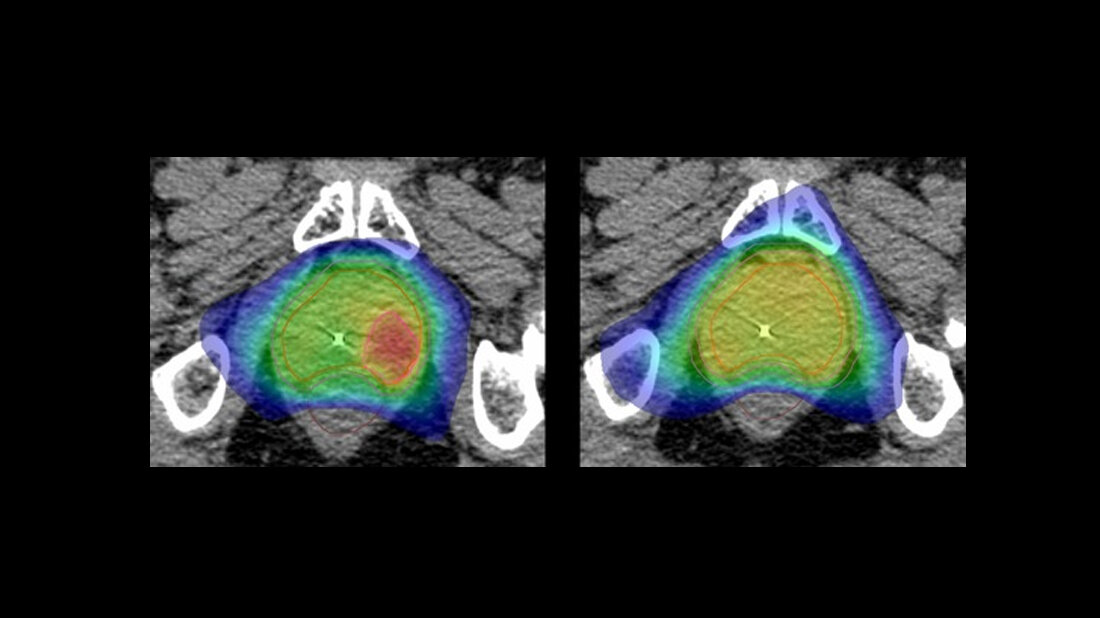

Statt wie bisher die gesamte Prostata gleichmäßig zu bestrahlen, werden im Rahmen der HypoFocal-SBRT-Studie zusätzlich gezielt jene Bereiche des Organs, in denen die hochpräzise Bildgebung den Tumor anzeigt, mit besonderer Intensität bestrahlt. Dadurch soll eine verbesserte, effektivere Therapie und Schonung des umliegenden Gewebes, wie Blase und Darm erreicht werden. Zudem verkürzt sich die Behandlungszeit deutlich.